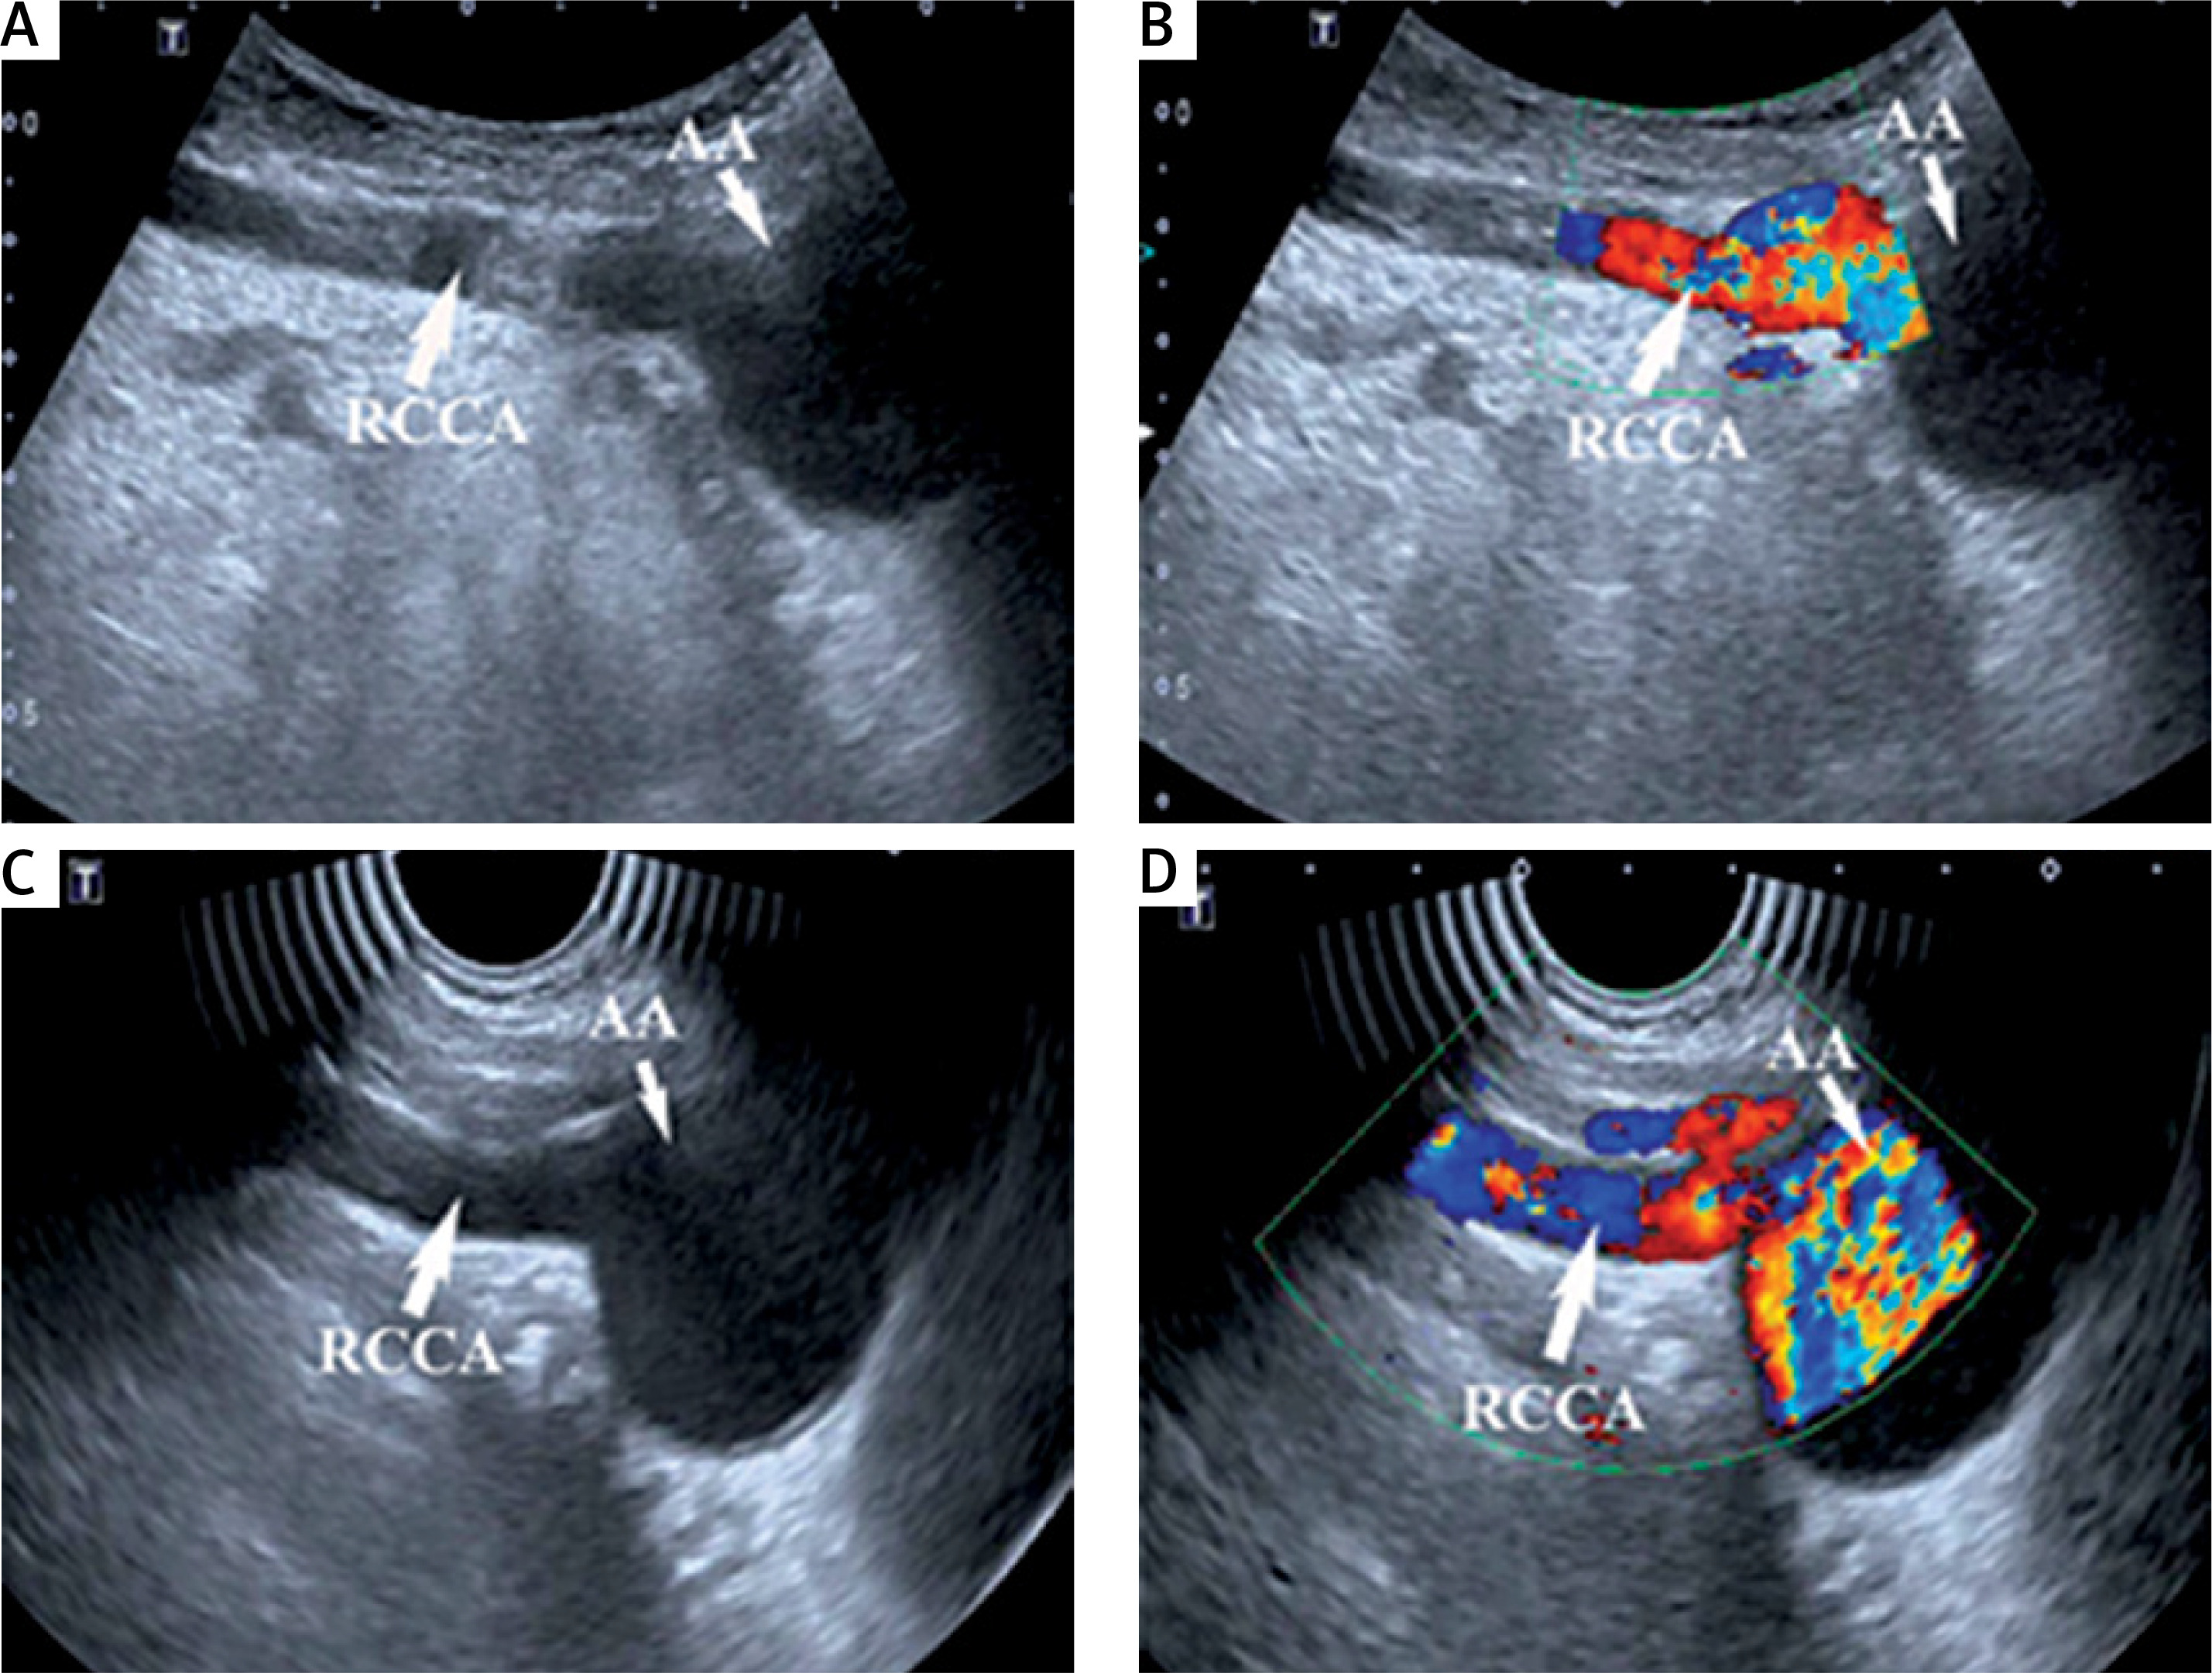

Figure 4

Aberrant right subclavian artery (ARSA) group. A, B – Scanning with transabdominal probe at the level of sternoclavicular joints, right common carotid artery (RCCA) originating directly from aortic arch is found. C, D – Scanning with intracavitary probe at the level of sternoclavicular joints, RCCA originating directly from aortic arch is found and the lumen is more clearly displayed. AA – aortic arch

After scanning with the transabdominal probe, intracavitary probe, or cardiac probe at the level of the sternoclavicular joints, the IA was found to be absent in all cases in the ARSA group (Figure 4). The RCCA and RSA routes gradually separated below the level of the sternoclavicular joints. Furthermore, 53 cases of RCCA that originated directly from the aortic arch were found, while the other 5 cases had a common stem, with the LCCA originating from the aortic arch.